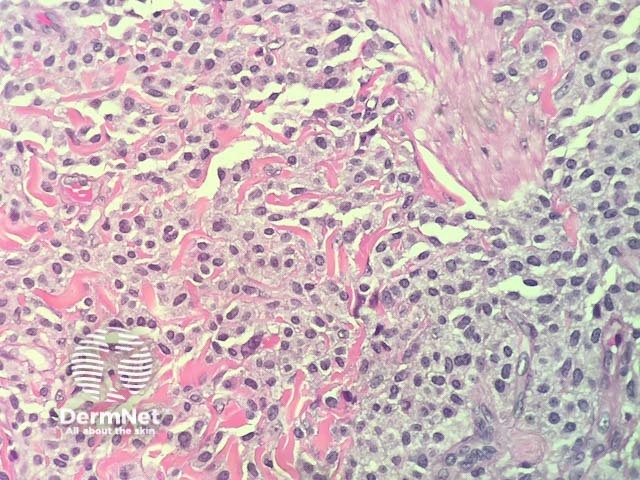

In maculopapular cutaneous mastocytosis, the histopathology shows an accumulation of mast cells in the dermis (figures 1-4). Mast cells are round or spindle shaped with abundant eosinophilic cytoplasm which contain minute granules, distinct cytoplasmic boundaries, and large pale nuclei (best seen in figures 2-4). Often there are accompanying other inflammatory cells including histiocytes, eosinophils and lymphocytes. There may be oedema of the dermis, particularly if the lesion has been traumatised.

Figure 2